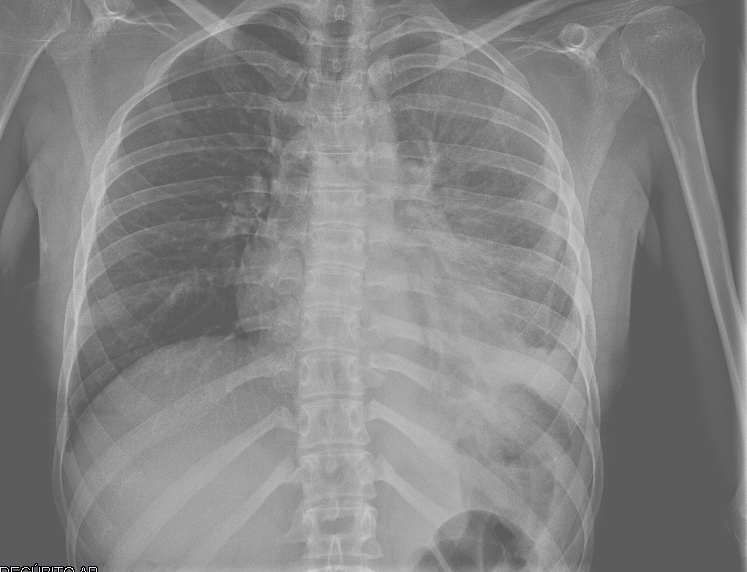

Ecografía torácica:

Derrame pleural izquierdo de 4 espacios intercostales, libre, hipoecogénico, sin ecos internos. Lóbulo pulmonar inferior izquierdo con imagen de patrón mixto (Intersticial y consolidación).